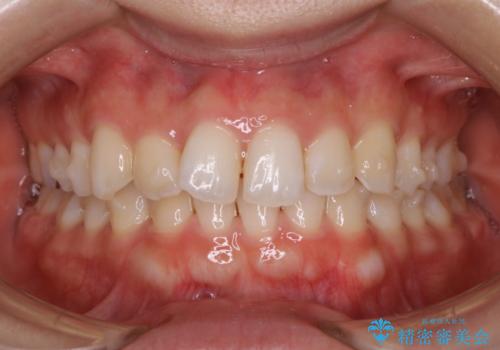

【非抜歯】下の前歯が1本少ない場合の矯正治療

- 前歯のガタつきを主訴に来院されました。

生まれつき下の前歯が1本少なく、その分のスペースを上の前歯がガタつくことで埋めているという状況でした。

上下それぞれのガタつきをとっていく過程で、歯1本分のスペースの差を、上顎の前歯のIPRで調整して並べる方法をご提案させていただきました。